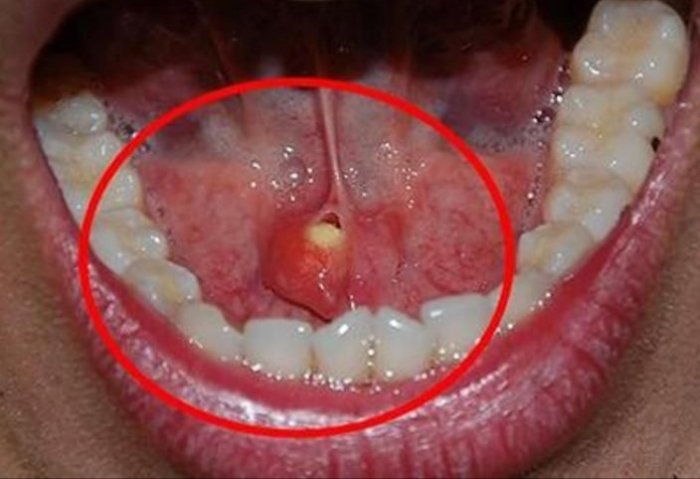

Tükürük bezi taşlarını, çene altında ve yanak arkasında yerleşen tükürük salgısı üreten tükürük bezlerinde veya tükürük bezlerinin ağız içine açılmasını sağlayan tükürük bezi kanallarında görülen taşlar olarak belirten KBB Uzmanı Doç. Dr. Nesrettin Fatih Turgut, “Tükürük bezi taşı tükürük içeriğinin yoğunluğu fazla olduğu için çene altı tükürük bezleri (submandibuler) ve kanallarında ve 30-60 yaş aralığında, erkeklerde daha fazla görülmektedir. Yetersiz sıvı alımı, tükürük salgısının azalmasına neden olan enfeksiyonlar, ilaç kullanımı ve çeşitli enfeksiyonlar ve tükürük bezi kanallarının darlıkları tükürük bezi kanalı içinde taş oluşmasına yatkınlık oluşturur. Bu hastalıkta tipik belirti, taşın var olduğu tarafta yer alan bezde yemek yeme sonrası gelişen şişlik ve ağrıdır. Tükürük salgısının dışarı atılamayıp birikimi, enfeksiyona yatkınlık oluşturur. Bakteriyel tükürük bezi iltihabı dediğimiz hastalık gelişebilir ki bu durumda şikayetler şiddetli hale gelebilir. Etkilenen tükürük bezinin aşırı şişmesi, aşırı hassasiyeti, ağrı ve ateş gelişebilir. Tedavi edilmediği takdirde, hastane yatışı gerektiren ve şiddeti daha fazla olan bir tabloya, derin boyun enfeksiyonuna, ilerleme görebiliriz” dedi.